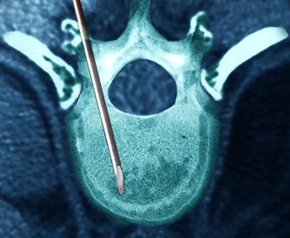

4無신경성형술

비수술 통증차단 치료법

신경차단술